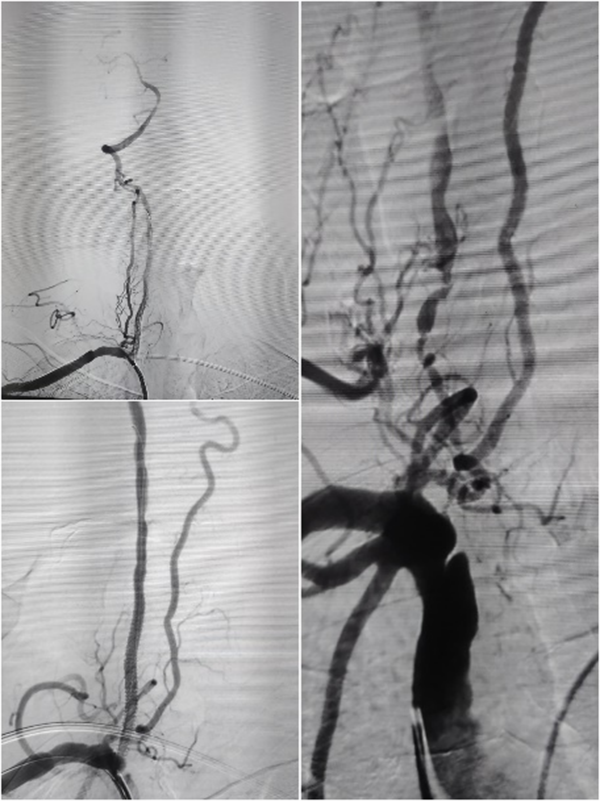

随着时间的推移,一例例复杂的全麻手术被成功完成:

高龄老人椎动脉长段次全闭塞

全麻下多支架再通术

接着又是两台颅外段头颈动脉支架植入术及7台脑血管造影术……

让我印象深刻的是位39岁的年轻男性患者,突发头晕伴右侧肢体麻木无力、言语不利,脑血管造影显示:椎动脉颅内段血管闭塞。患者病情复杂,血管闭塞节段长,而且血管条件差,开通闭塞血管的手术风险也相应增加,但如果选择保守治疗,将来发生严重卒中的风险非常高。